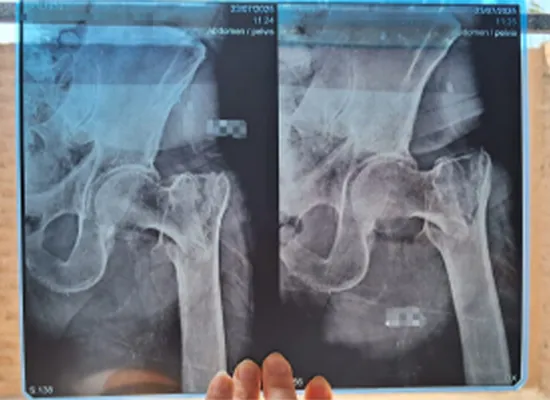

Imaging radiographic dikonfirmasi narekahan intertrochanteric kénca lunta , merlukeun campur bedah timely mulangkeun stabilitas jeung mobilitas.

X-ray preoperative némbongkeun lunta narekahan intertrochanteric kénca di penderita manula, Lima Peru

X-ray pasca operasi nunjukkeun fiksasi kuku Intertan Intramedullary tina narekahan intertrochanteric kénca, Peru